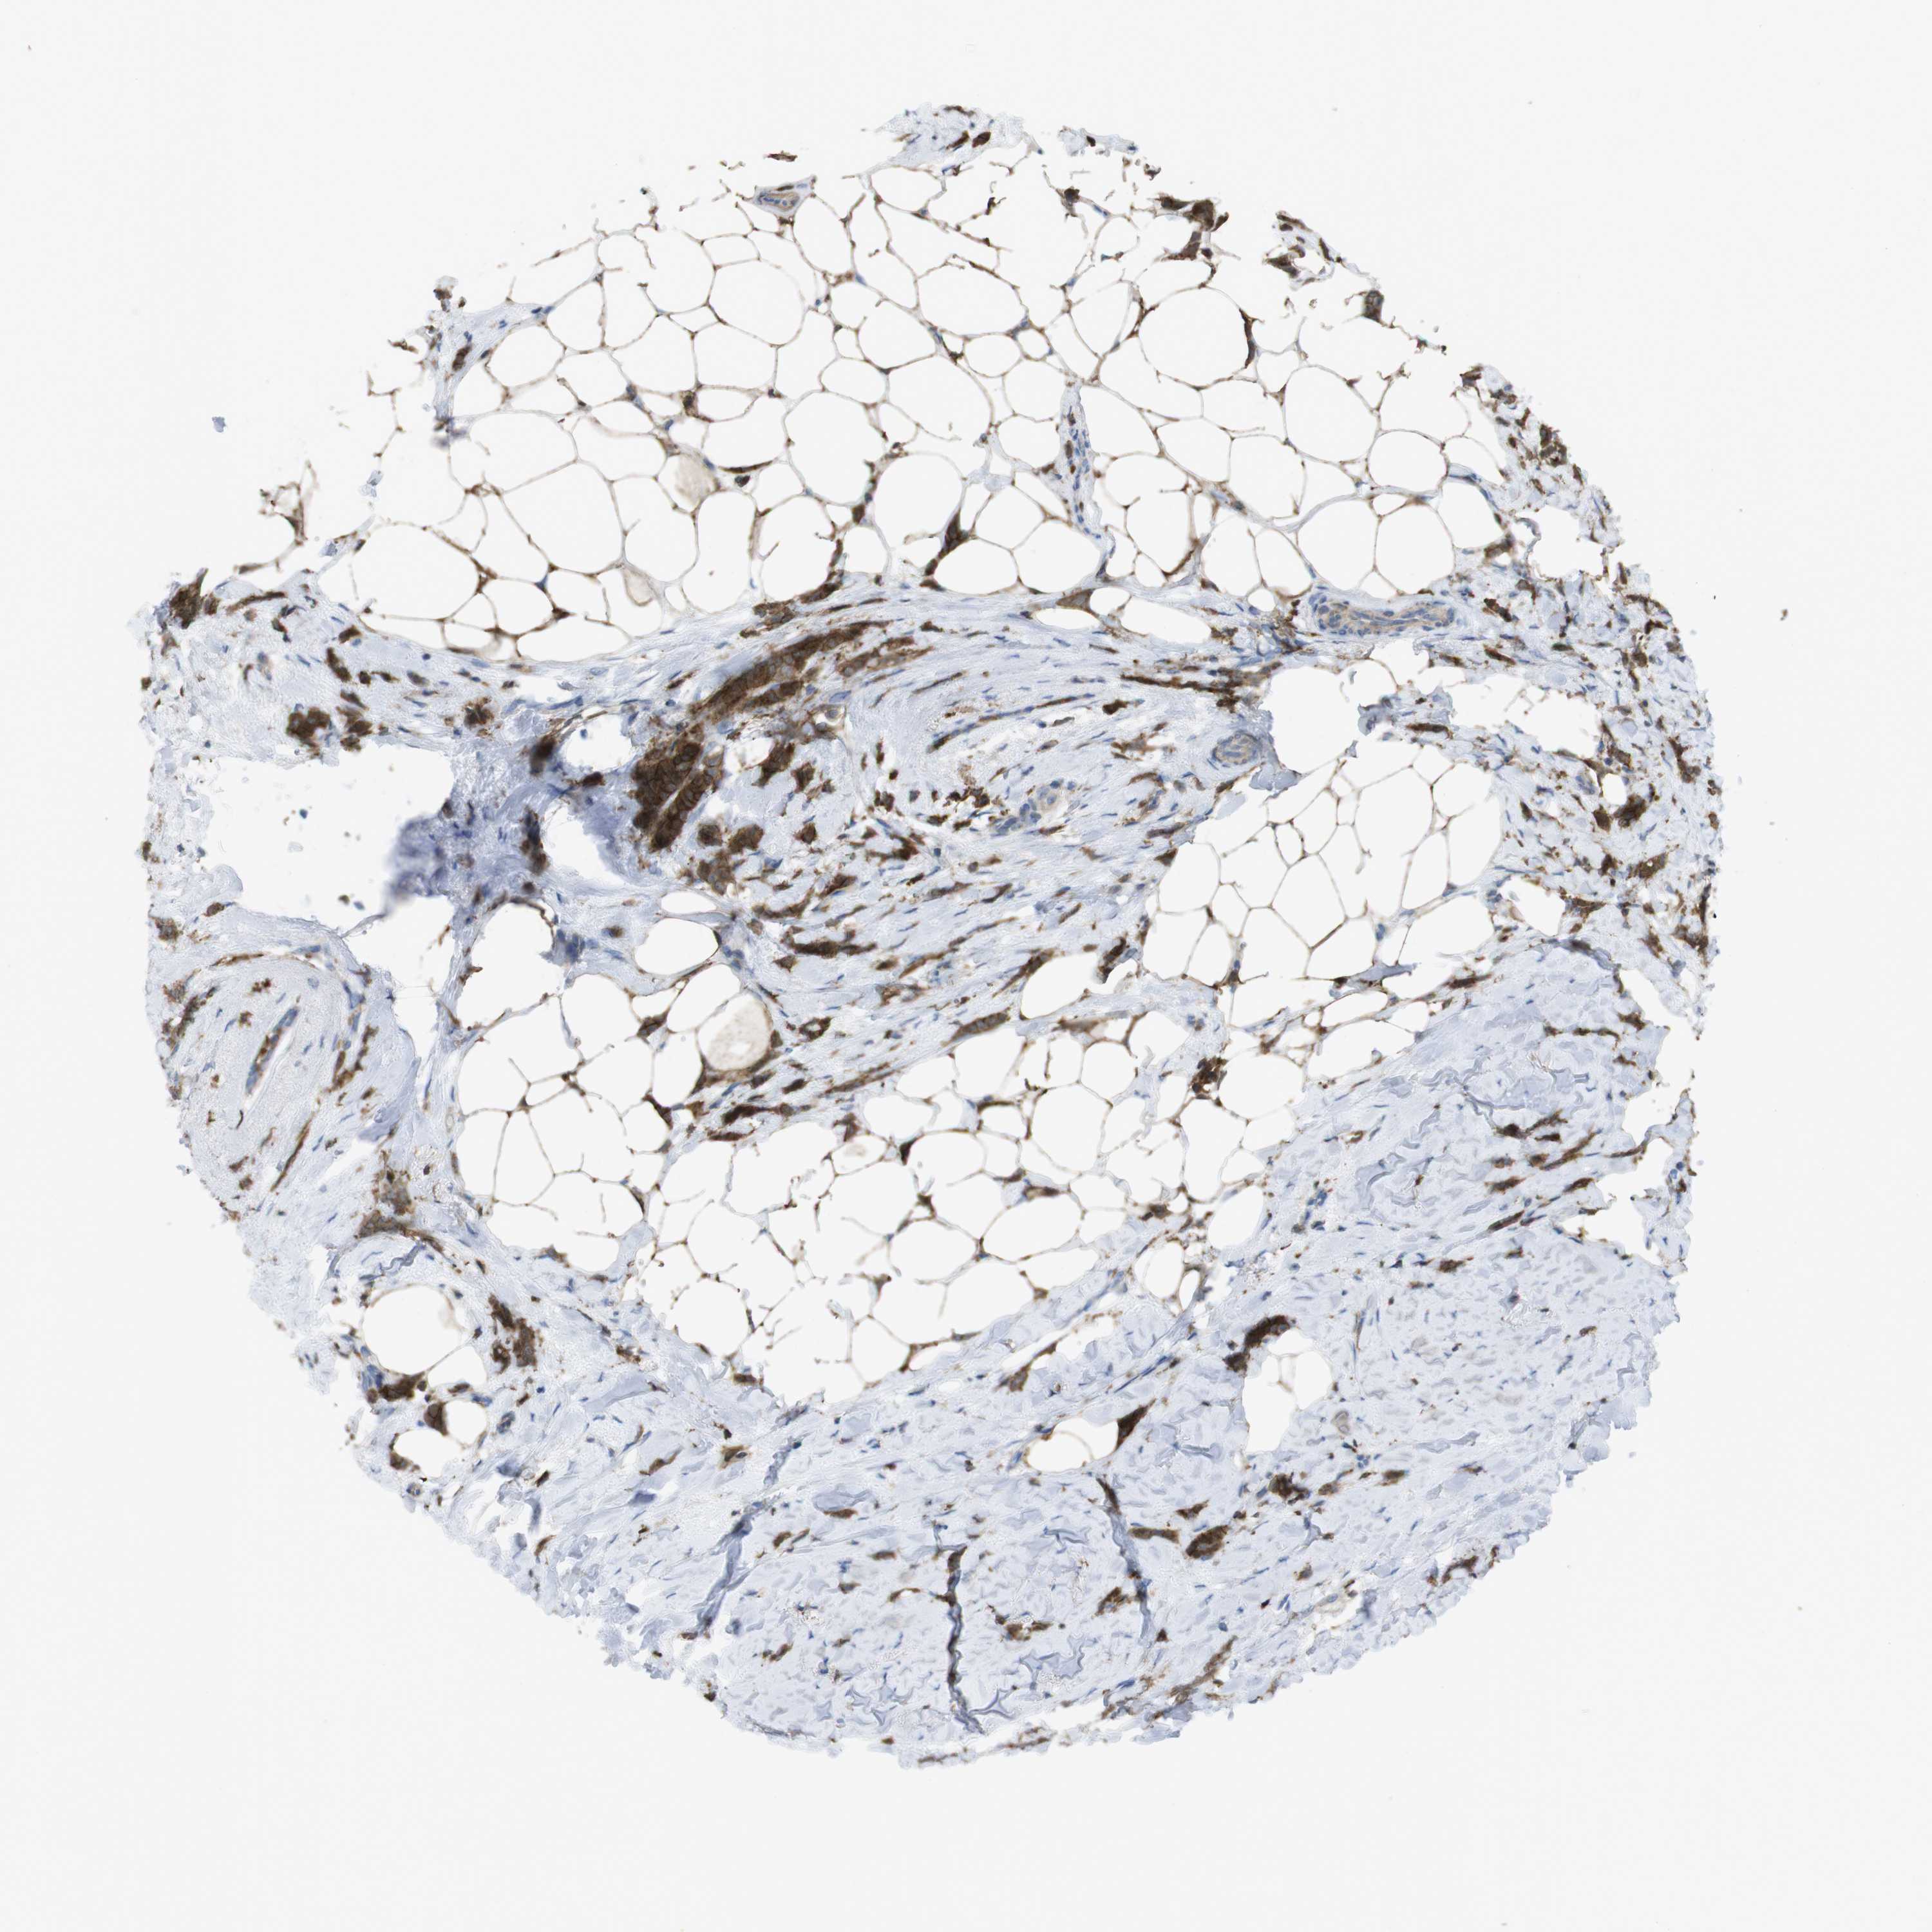

CANCER BREAST CANCER Show tissue menu

BRCA TCGA BRCA VALIDATION PROTEIN EXPRESSION

ANTIBODIES

AND

VALIDATION